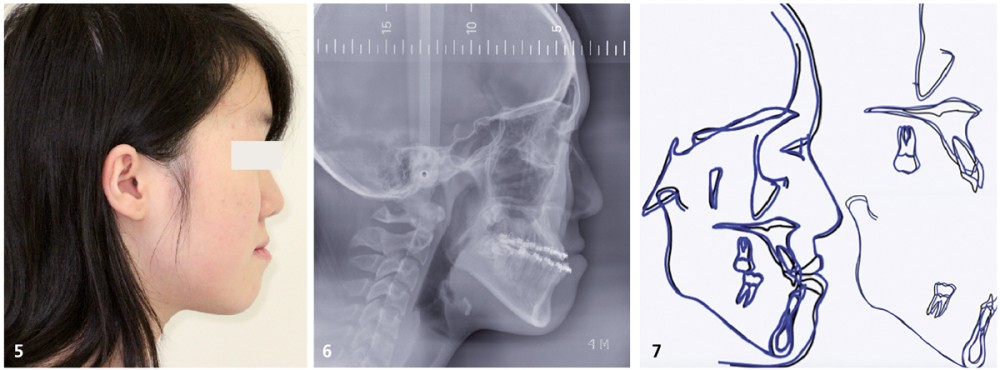

Traitement multi-attaches (fig. 4, 5, 6 et 7)

Une fois les espaces d’extractions fermés, nous avons poursuivi le nivellement avec des arcs aciers .016x.022 puis .018x.025 afin de programmer la chirurgie orthognathique.

De plus, ce choix thérapeutique permet, dans l’éventualité d’une récidive tardive…